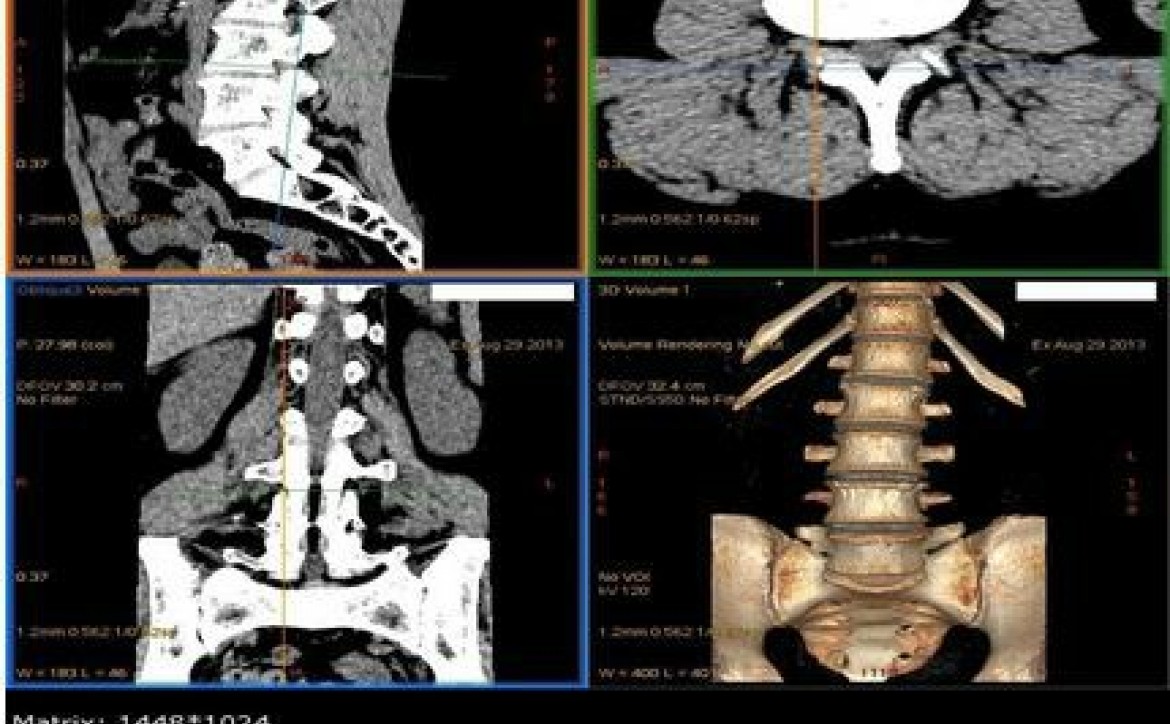

Image scanner d'un rachis lombaire

Scanner à l'ICM